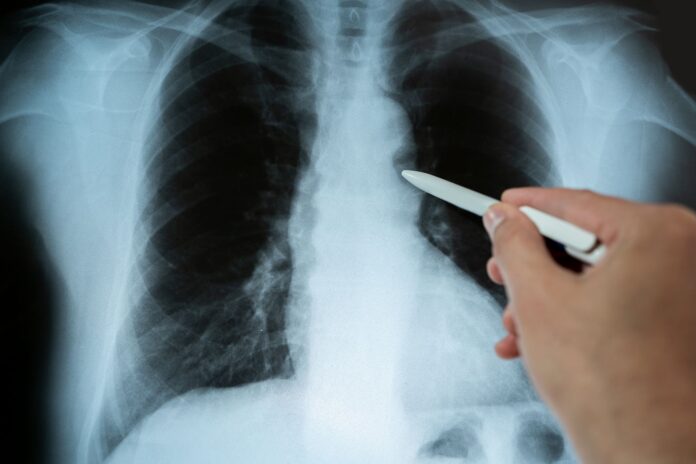

Pierwszym badaniem jest zwykle RTG klatki piersiowej, które może wykazać cień guza lub asymetrię w szczytach płuc. Ze względu na nakładające się struktury kostne, jego czułość w tej lokalizacji jest jednak ograniczona.